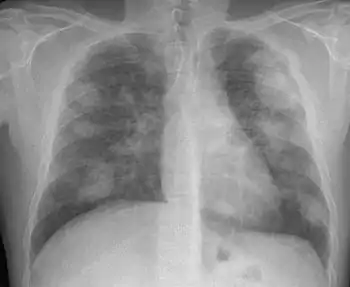

السحار السيليسي (بالإنجليزية: Silicosis) (سيليكوسيس) شكل من أشكال أمراض الرئة المهنية الناجمة عن استنشاق غبار السيليكا البلورية. يتميز بالتهاب وتندب يأخذ شكل آفات عقيدية في الفصوص العليا للرئتين. وهو أحد أشكال تغبر الرئة.[1] يتميز السحار السيليسي (خاصة الشكل الحاد) بضيق في التنفس وسعال وحمى وزرقة (جلد مزرق). غالبًا ما يُشخص بشكل خاطئ على أنه وذمة رئوية (سائل في الرئتين) أو ذات رئة أو مرض السل.